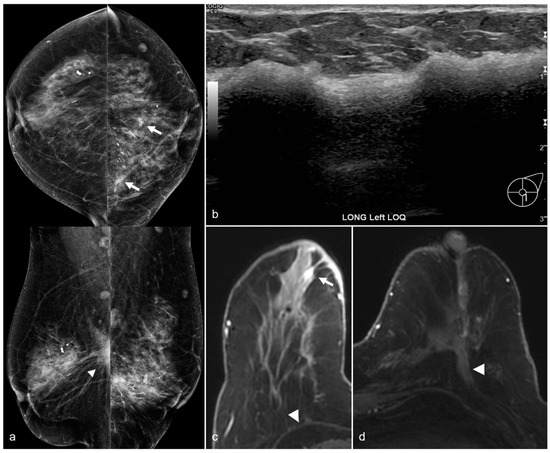

Figure 15. A 79-year-old woman with a history of subglandular silicone implants with a remote history of BES. Mammography (a) demonstrates dense masses in the left breast (arrows) and a right prepectoral asymmetry (arrowhead). Four biopsy clips are also seen in the left breast secondary to prior benign biopsies. Longitudinal left breast ultrasound (b) demonstrates an extensive snowstorm appearance, which limits evaluation of the breasts. T1-weighted post-contrast axial MRI (c) reveals an enhancing 0.3 cm focus in the right central breast (arrow). Subsequent MRI-guided biopsy revealed multifocal LCIS and ALH, and the patient underwent breast conservation therapy. Note the post-BES changes in the bilateral prepectoral regions (arrowheads), which is more pronounced in the left breast (d).